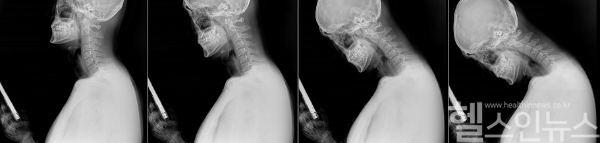

길을 걸을 때도, 지하철이나 버스에서도 스마트폰에 푹 빠져 있는 사람들을 흔히 볼 수 있다. 정보와 재미를 손 안에서 모두 얻을 수 있는 스마트폰은 SNS, 게임, 쇼핑뿐 아니라 업무적인 소통 등 모든 일상생활에 필요하기 때문이다. 하지만 장시간 고개를 숙인 채 구부정한 자세를 유지하는 것은 필연적으로 목과 척추 건강에 악영향을 끼친다. 고개를 숙이면 머리가 떨어지지 않도록 붙잡는 목 근육의 수축력이 함께 작용하면서 목에 가해지는 무게는 머리 무게의 5배에 이른다. 성인 기준 머리 무게가 5kg이라면 목에 가해지는 무게는 무려 25kg이 되는 셈이다.